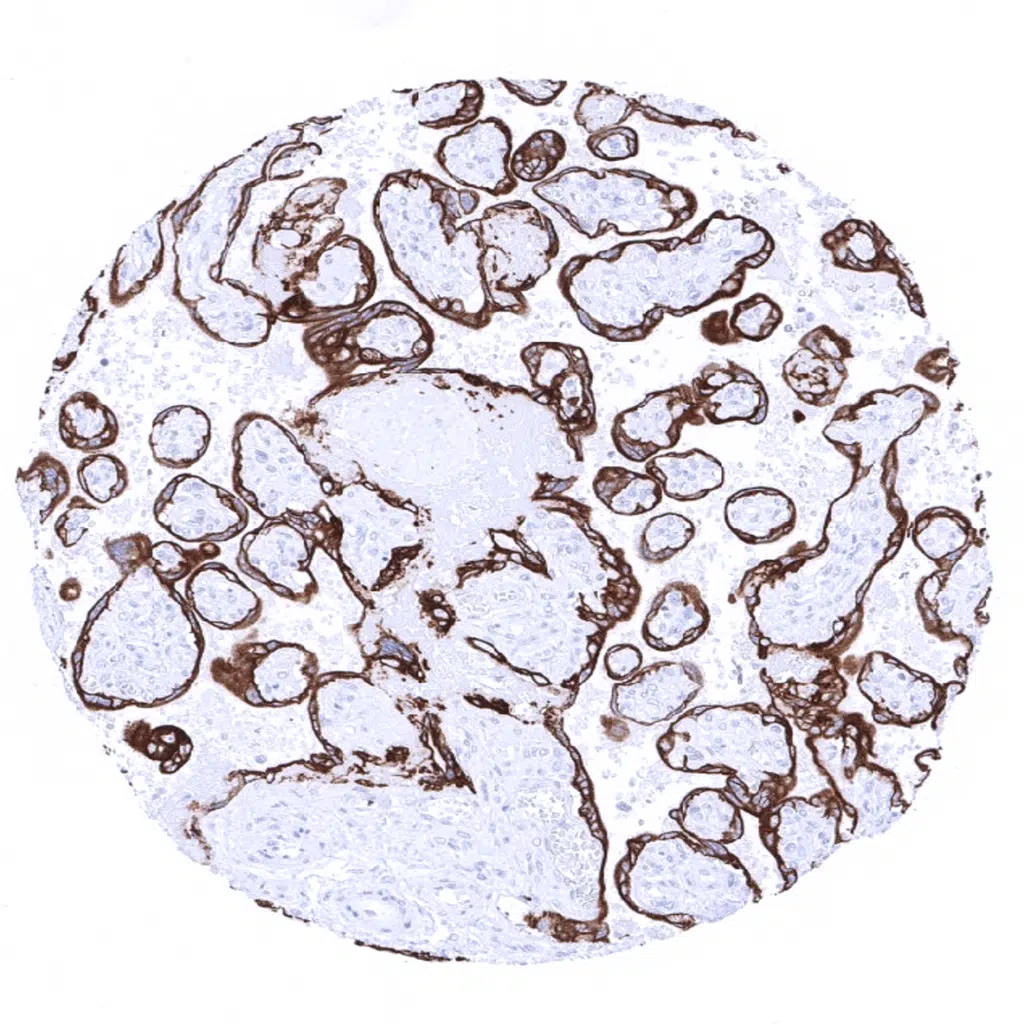

Placenta, mature - The syncytiotrophoblast, and to a somewhat lesser extent the cytotrophoblast of the placenta are Cytokeratin 19 positive.